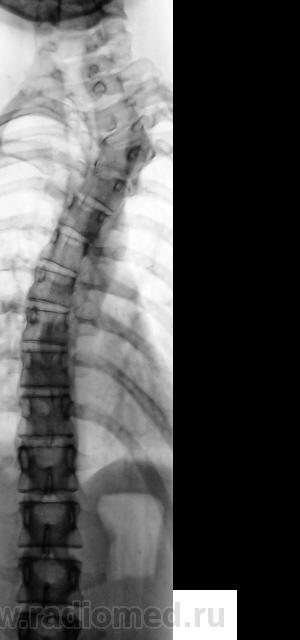

Подросток направлен в рентгеновский кабинет с диагнозом "сколиоз"...

Ну что же, сколиоз есть.

Сколиоз-то сколиоз, но генеза "аномального".

Это синостоз тел верхних шейных позвонков и С6-С7? И боковые клиновидные полупозвонки в верхнегрудном отделе? Это синдром Клиппеля-Файля? А может и Шпренгеля...

Поражает, что только сейчас выявлена такая выраженная дисплазия..там видимо и по органам проблемм хватает..